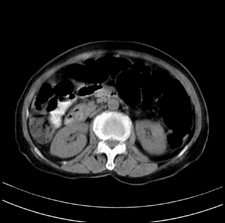

患者,女,75岁。腹痛,体黄5日,膝胸位时腹痛缓解。肝功能明日出来。彩超提示胆总管占位,未见血流信号。心电图提示s-t段改变。患者体质较弱,未能增强。

胆总管多发结石伴肝内外胆管轻度扩张。

胆总管上段,腔内有软组织密度影 ,ct值36-44hu。大家看有没有胆管癌的可能。

2楼所说胰腺内钙化不像,象脾脏血管的钙化

典型胆总管多发结石;增强扫描前后ct值是否发生改变是鉴别结石与占位的依据。

典型的胆总管多发结石。在没有增强的情况下,暂不考虑其他。

胆管没有鼠尾征,还是考虑结石